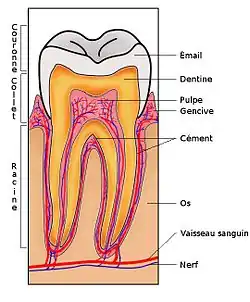

La parodontie est la partie de la dentisterie qui est spécialisée dans le traitement du parodonte, c'est-à-dire les tissus de soutien de la dent : gencive, tissu osseux, cément et ligament parodontal.